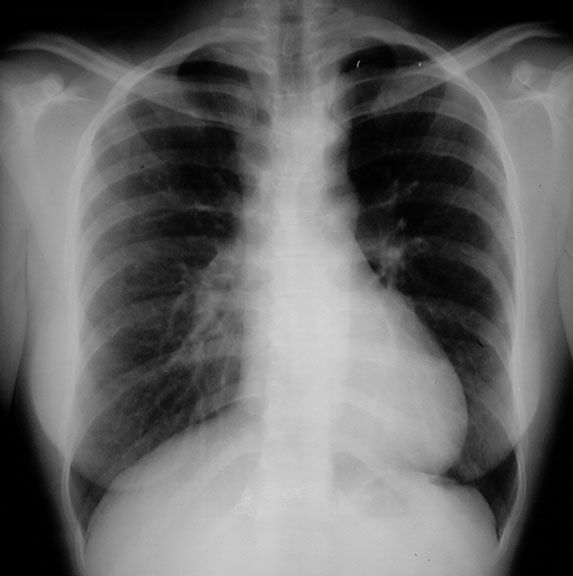

Coarctation Aorta

• Post stenotic dilatation: Mogul sign

• Rib notching: Difficult to see in this presentation